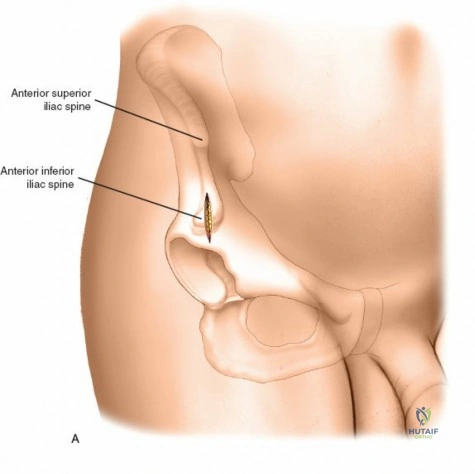

Wrist and Metacarpal Safe Zones

For spanning wrist fixators, distal pins are placed in the second metacarpal. The safe zone is the dorsoradial aspect of the second metacarpal base and shaft. The first dorsal interosseous muscle and extensor tendons must be respected. The radial artery courses proximally in the anatomic snuffbox and must be avoided during basal metacarpal pin insertion.

Metacarpal Pin Placement

1. Make two 1 cm incisions over the dorsoradial aspect of the second metacarpal.

2. Dissect bluntly, protecting the dorsal sensory branches of the radial nerve and the extensor tendons.

3. Place the tissue sleeve at a 45-degree angle to the dorsal and lateral planes to maximize purchase in the metacarpal shaft.

4. Pre-drill and insert two 3.0 mm pins.

Proximal Radius Pin Placement

1. Make incisions over the dorsolateral aspect of the radius, approximately 10-12 cm proximal to the radiocarpal joint.

2. Dissect bluntly to avoid the SRN.

3. Insert two 4.0 mm pins.